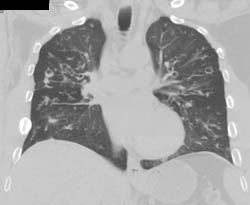

Bronchiectasis